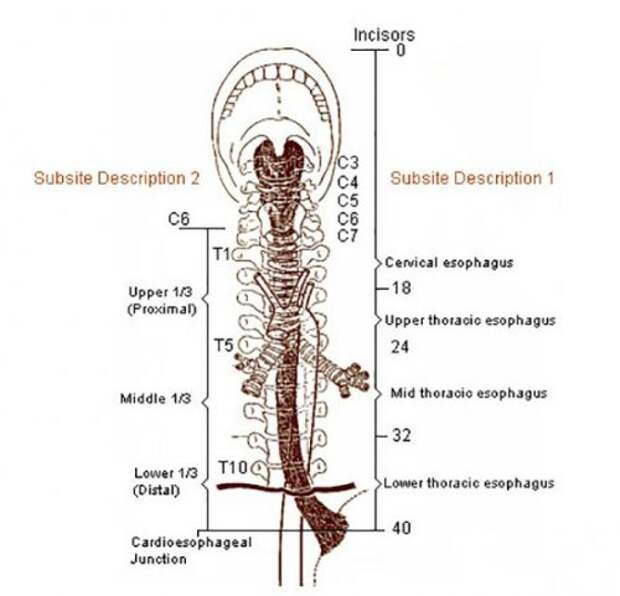

10. Пищевод перенаправляет пищу из ротовой полости в желудок, и в этой миссии ему помогают специальные мышцы. Процесс «доставки» называется перистальтикой глотания.

10. Пищевод перенаправляет пищу из ротовой полости в желудок, и в этой миссии ему помогают специальные мышцы. Процесс «доставки» называется перистальтикой глотания.